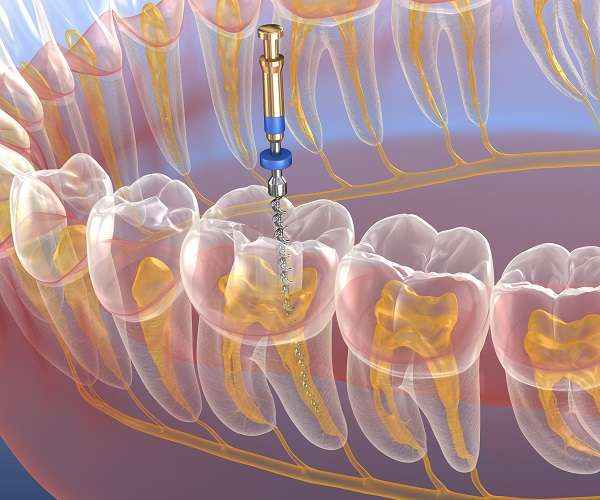

Root canal dental restorations involve a few key steps, starting with the application of a numbing agent. Next, the infected pulp is carefully removed so that the cavity can be cleaned and disinfected. To finish, the tooth will be sealed with gutta-percha, a rubbery material used in dentistry. A temporary crown will be placed to complete the dental restoration, however, a few weeks later, a permanent one can be placed.